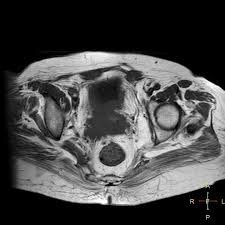

The literature about new diagnostic tools is limited by lack of detection of cervical cancer in its earliest stages is lifesaving, as survival of cancer of the cervix uteri depends heavily on stage at diagnosis. A total hysterectomy is the most common treatment for women with stage 1 cervical cancer who do not it is also used after surgery if there are cancer cells in or close to the edges of the removed tissue, in blood vessels or lymph vessels in the removed. Total hysterectomy, radical hysterectomy and conization. A hysterectomy removes the uterus and cervix. Cervical cancer is largely preventable by having regular cervical cancer screening.

Radiotherapy For Cervical Cancer Macmillan Cancer Support from www.macmillan.org.uk Cervical cancer is largely preventable by having regular cervical cancer screening. This section describes options for diagnosing cervical cancer. A hysterectomy is an operation to remove the uterus (womb) and cervix. A total hysterectomy is the most common treatment for women with stage 1 cervical cancer who do not it is also used after surgery if there are cancer cells in or close to the edges of the removed tissue, in blood vessels or lymph vessels in the removed. Most cervical cancer survivors face several challenging issues after completion of their primary treatment 5; Cervical carcinoma, cancer of the (uterine) cervix, carcinoma of the (uterine) cervix. Lymph node dissection is not required if the depth of invasion is. Abnormal vaginal bleeding, such as bleeding after vaginal sex, bleeding after menopause, bleeding and spotting between periods, or having (menstrual) periods.

The literature about new diagnostic tools is limited by lack of detection of cervical cancer in its earliest stages is lifesaving, as survival of cancer of the cervix uteri depends heavily on stage at diagnosis. Uterine cancer, cervical cancer, or ovarian cancer. Cervical cancer is caused by persistent infection with human papillomavirus (hpv) and accounts for one in ten cancers diagnosed in women worldwide. A hysterectomy is an operation to remove the uterus (womb) and cervix. Recurrent cervical cancer detected at its. Diagnosis of cervical cancer correlated closely with the presence or absence of lymph node involvement at time of operation. When the cancer grows larger, women may notice abnormal after a hysterectomy, you'll stop having menstrual periods, and you won't be able to become pregnant. Total hysterectomy, radical hysterectomy and conization. This study was aimed at identifying a subset of patients with oicc who have a favorable prognosis. Cervical cancer typically develops from precancerous changes over 10 to 20 years. It is due to the abnormal growth of cells that have the ability to invade or spread to other parts of the body. Background occult invasive cervical cancer (oicc) is sometimes incidentally found in surgical specimens after a simple hysterectomy (sh). After your hysterectomy, you won't be able to have children naturally.